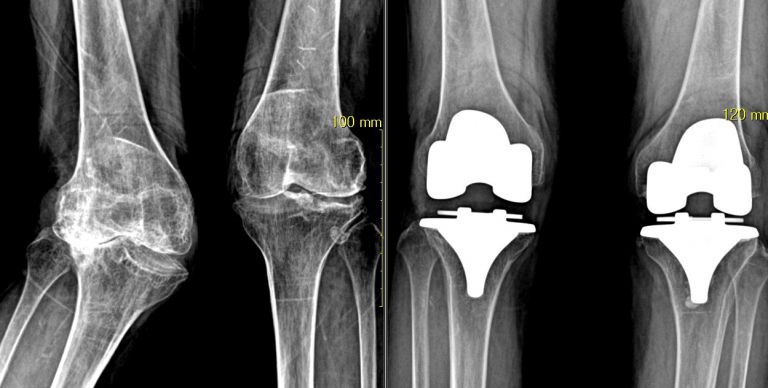

인공관절 재치환술